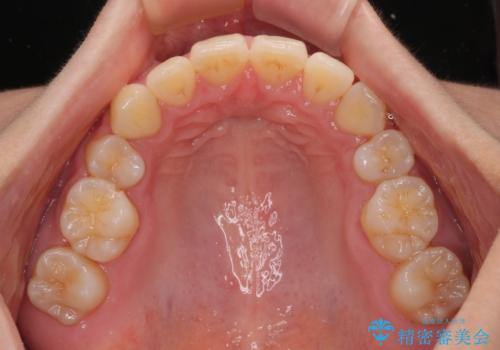

全顎的なデコボコと口元の突出感 ワイヤー装置での抜歯矯正で整った口元に

- 奥歯も含めて全体的なデコボコと前歯の突出感を気にして来院された患者様です。

上下左右第一小臼歯4本を抜歯し、ワイヤー装置にて矯正治療を行うこととしました。

想像以上に咬合力が強く、抜歯したスペースを閉じきるまでに長期間を要することとなりました。

前歯の突出感がなくなり、仕上がりには大変満足していただけました。